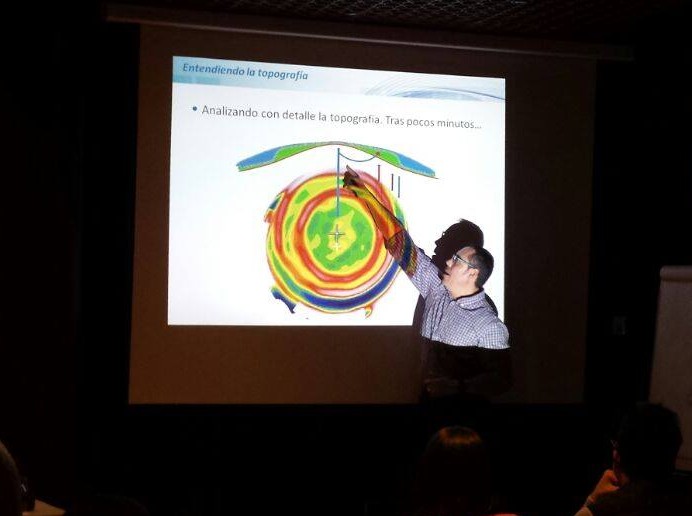

El objetivo principal del curso era plantear distintas situaciones donde el Ortoqueratologista debe analizar los problemas que pueden surgir durante la adaptación y valorar que opciones puede adoptar para darles solución.

El curso fue desarrollado con un carácter puramente práctico y se analizaron gran cantidad de fluorogramas y topografías tras tratamiento con OrtoK entre todos los asistentes.